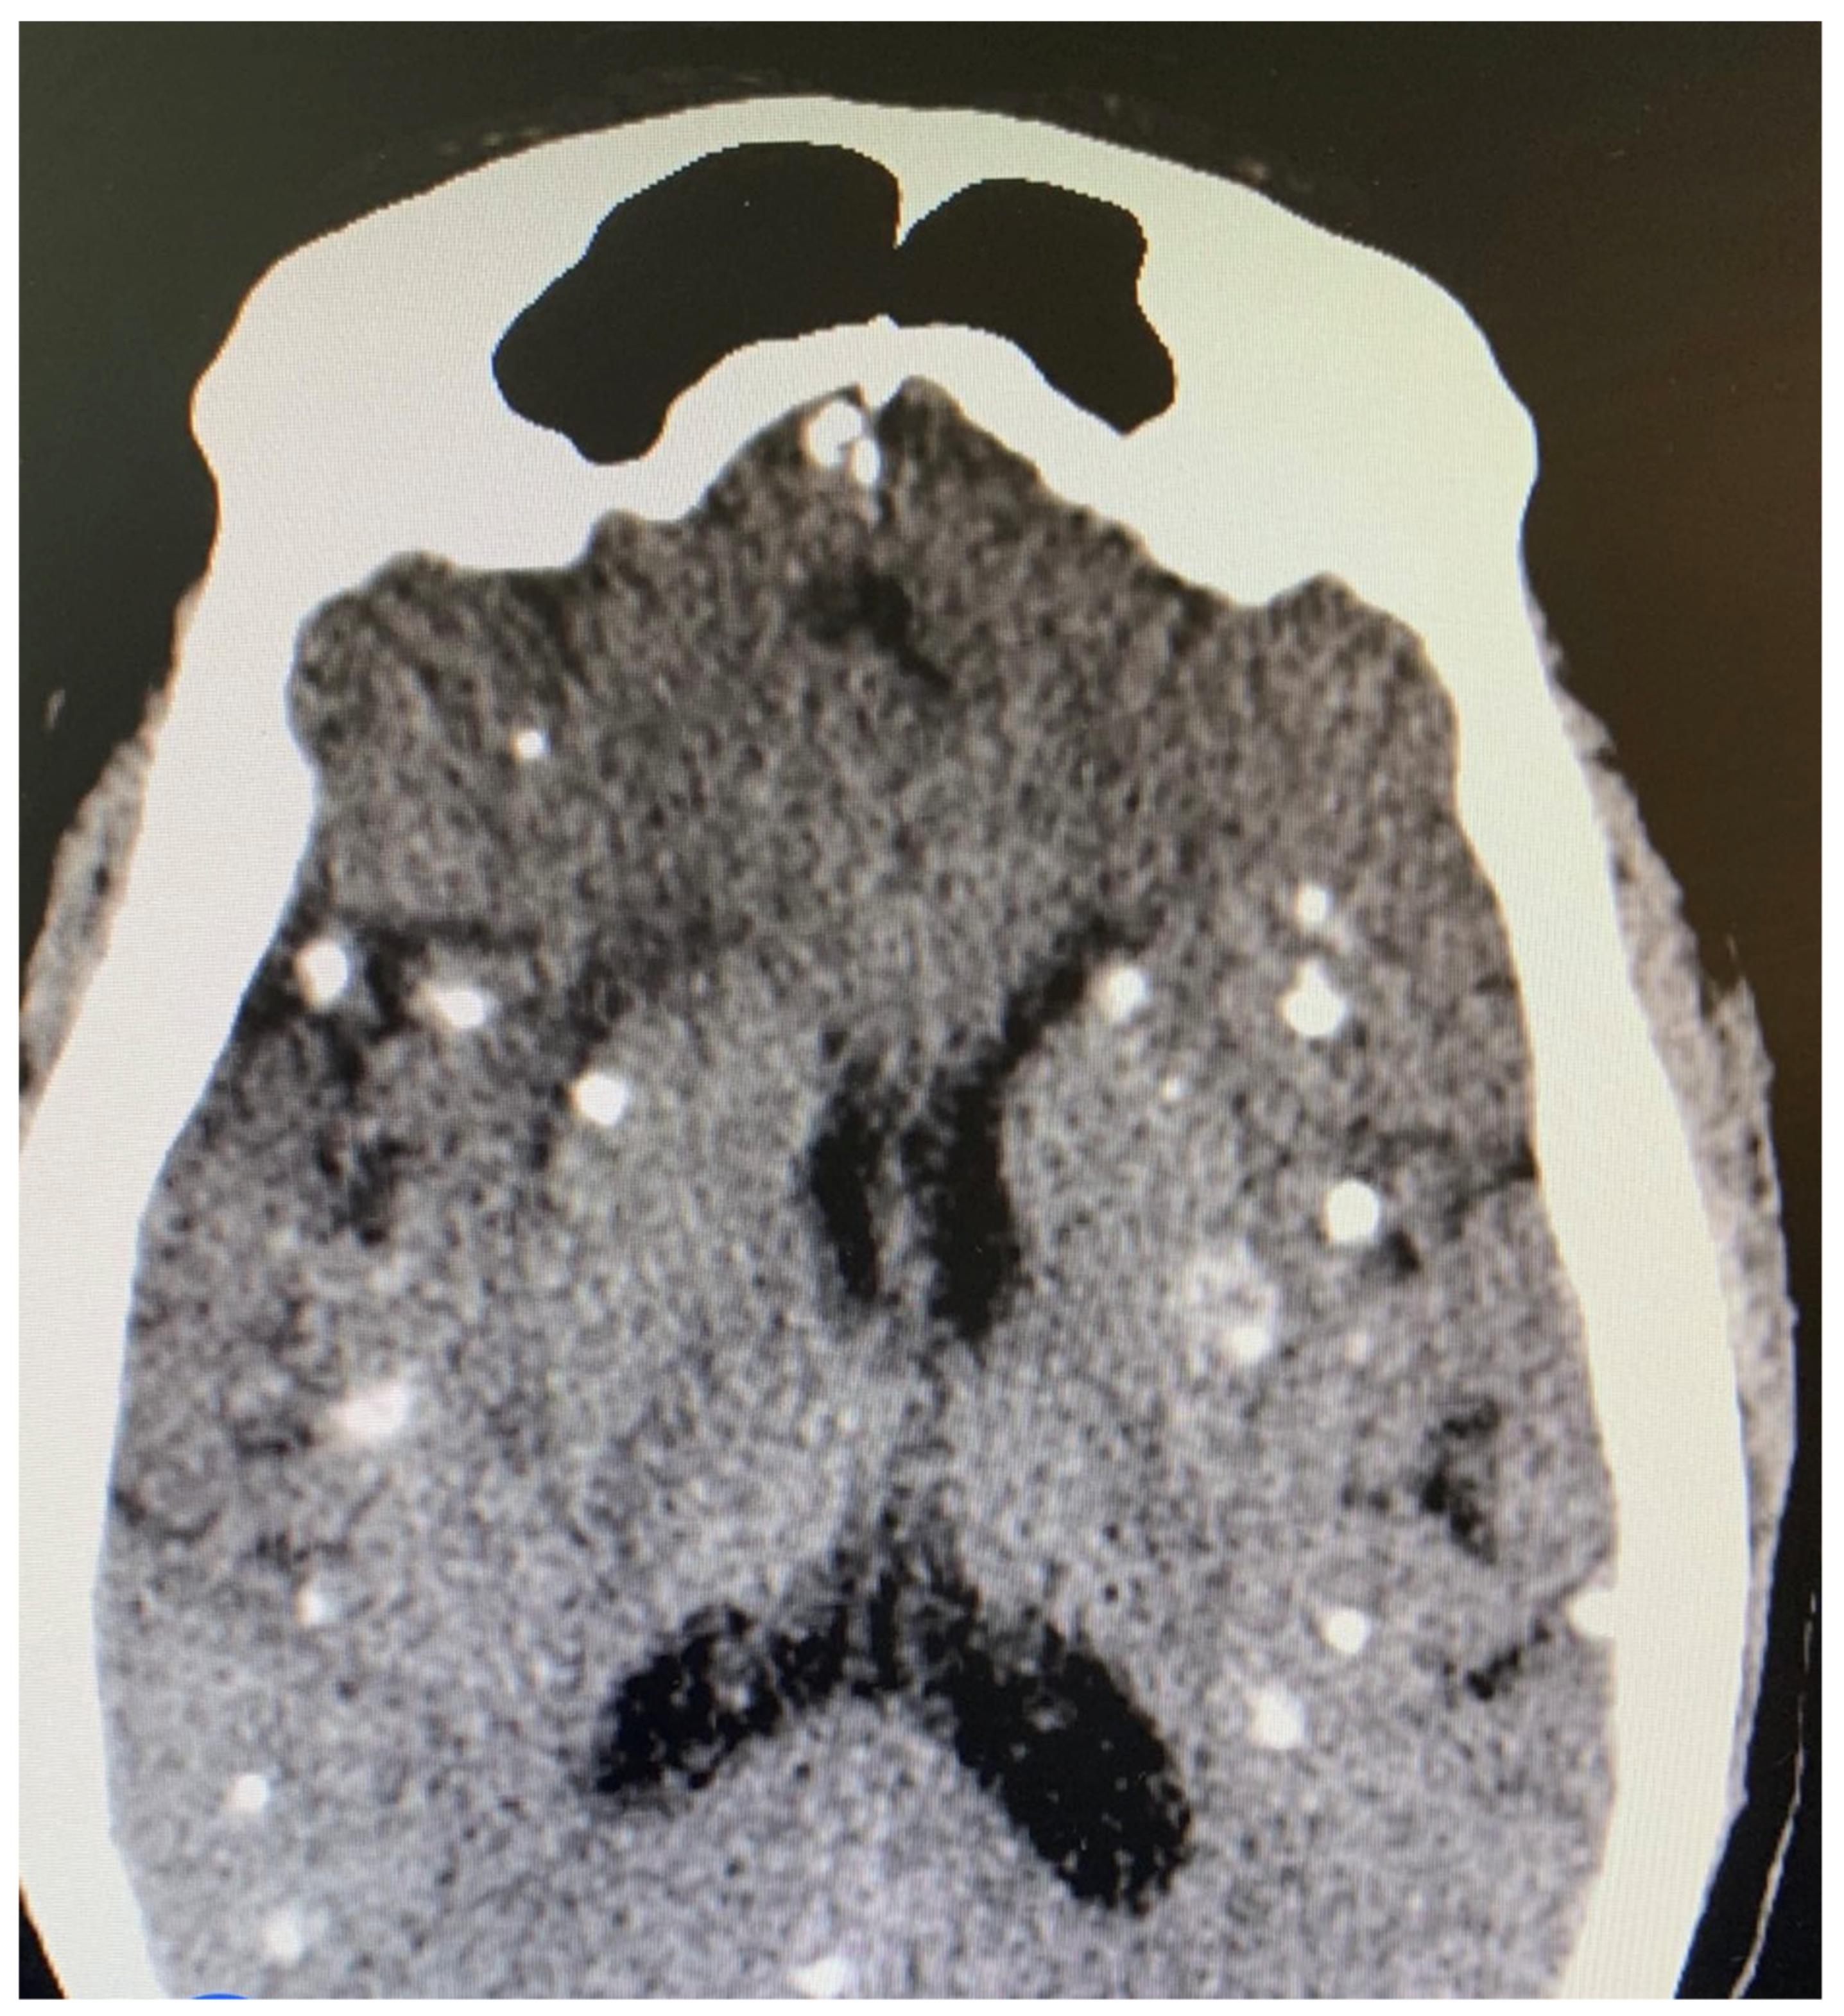

Several diagnostic tests were performed, including complete blood count, urinalysis, stool microscopy test Figure 1, and cerebrospinal fluid analysis Table 1. Serology testing (enzyme-linked immuno-electrotransfer blot) of blood for cysticercosis antibodies to glycoprotein antigens was positive, suggesting cysticercosis. Head computed tomography (CT) scan showed local soft tissue inflammation and multiple cysticerci granulomas due to cysticerci degeneration in the cerebral cortex Figure 2. Brain magnetic resonance angiography (MRA) showed a wedge-shaped T1-weighted hypointense and T2-weighted hyperintense lesion in the body of the right caudate nucleus. Diffusion of contrast was restricted on diffusion-weighted imaging. The lesion measured 2.3 cm in diameter and was suggestive of an acute/subacute infarct Figure 3. There was no restriction of contrast diffusion on DW1, suggesting white matter changes. A final diagnosis of cortical blindness due to NCC and co-infection with a urinary tract infection was made.

Figure 2.

Head CT scan showing multiple cysticerci in the cerebral cortex.